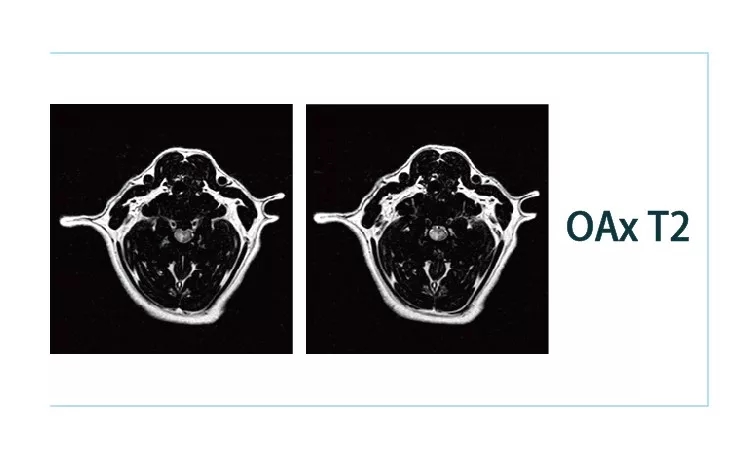

【朗润影像档案】20181221磁共振影像病例结果讨论

640.webp.jpg640.webp (1).jpg